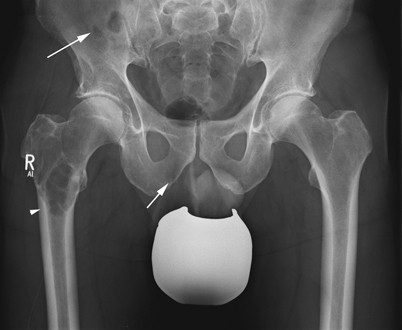

Datei Osteolyse Nach Huft Tep Jpg Wikipedia

Rapid Acetabular Chondrolysis Following Hemiarthroplasty Of The Hip A Poor Prognostic Sign